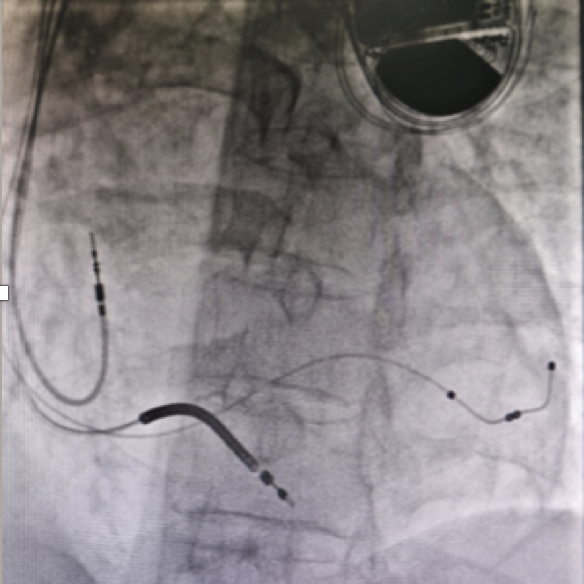

心内科为患者针对性完善了心电图、动态心电图和心脏影像的检查,其中心脏超声和核磁共振都检测到了Fabry病心脏受累的特征性表现,包括心房扩大、心肌肥厚以及相应部位的纤维化改变,并且患者心脏收缩和舒张功能都出现明显下降,射血分数不足35%,伴有心脏收缩失同步。经过心内科全科查房讨论,决定在药物治疗基础上,为患者植入CRT-D。在盛琴慧主任医师的精心操作下,手术顺利完成(图2)。患者的心电图提示起搏器功能良好,超声心动提示心脏收缩功能明显改善。伴随心功能的改善,患者的特异性酶替代治疗是针对患者病因治疗的最重要手段。2018年Fabry病进入我国首批罕见病目录,2022年该病的特异性酶替代疗法与其他6种罕见病用药一起进入国家医保目录, MDT专家们决定乘胜追击,继续为患者应用酶替代治疗(图3)。

图2 CRT-D起搏器植入及植入术前术后心电图